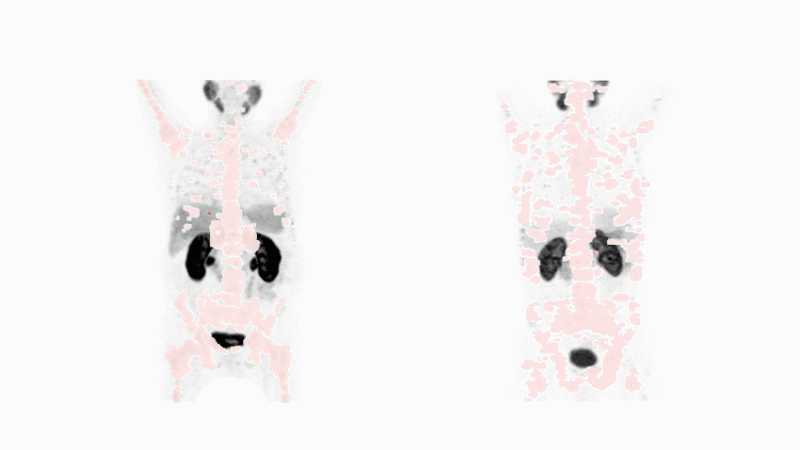

La médecine nucléaire présente aussi une composante diagnostique. Elle utilise la même molécule spécifique de la tumeur qu’en oncothérapie mais délivre des atomes radioactifs qui ont le pouvoir d’identifier et de localiser le cancer. Ces atomes émettent des rayons gamma qui sont détectés à l’aide de scanners spéciaux. Si le médicament débusque le cancer recherché, ce dernier sera révélé et ce, peu importe où il se niche dans l’organisme. Cela s’applique même à de minuscules zones impossibles à exciser par un chirurgien. Photo de Michael Hofman, avec l’aimable autorisation du Journal of Nuclear Medicine. Animation de Fidelis Onwubueke

La médecine nucléaire présente aussi une composante diagnostique. Elle utilise la même molécule spécifique de la tumeur que l’agent thérapeutique pour identifier le cancer et le localiser.

Ces atomes dégagent une forme d’énergie n’occasionnant que peu de dégâts. Elle s’apparente à une onde lumineuse qui peut être détectée ex vivo par des scanners. A présent, les médecins peuvent voir le cancer, peu importe l’endroit où il s’est propagé dans l’organisme.

Ce n’est que lorsque les pièces du puzzle moléculaire s’imbriquent que le diagnostic peut révéler le cancer d’un patient. Si tel est le cas, une thérapie ciblée par radioligand avec la même molécule spécifique de la tumeur constitue une option thérapeutique appropriée.

Cette approche diagnostique et thérapeutique permet aux médecins de choisir le médicament adapté à la forme de cancer spécifique au patient. Les futurs scanners peuvent en outre aider les médecins à déterminer l’efficacité du médicament et à faire progresser le traitement.